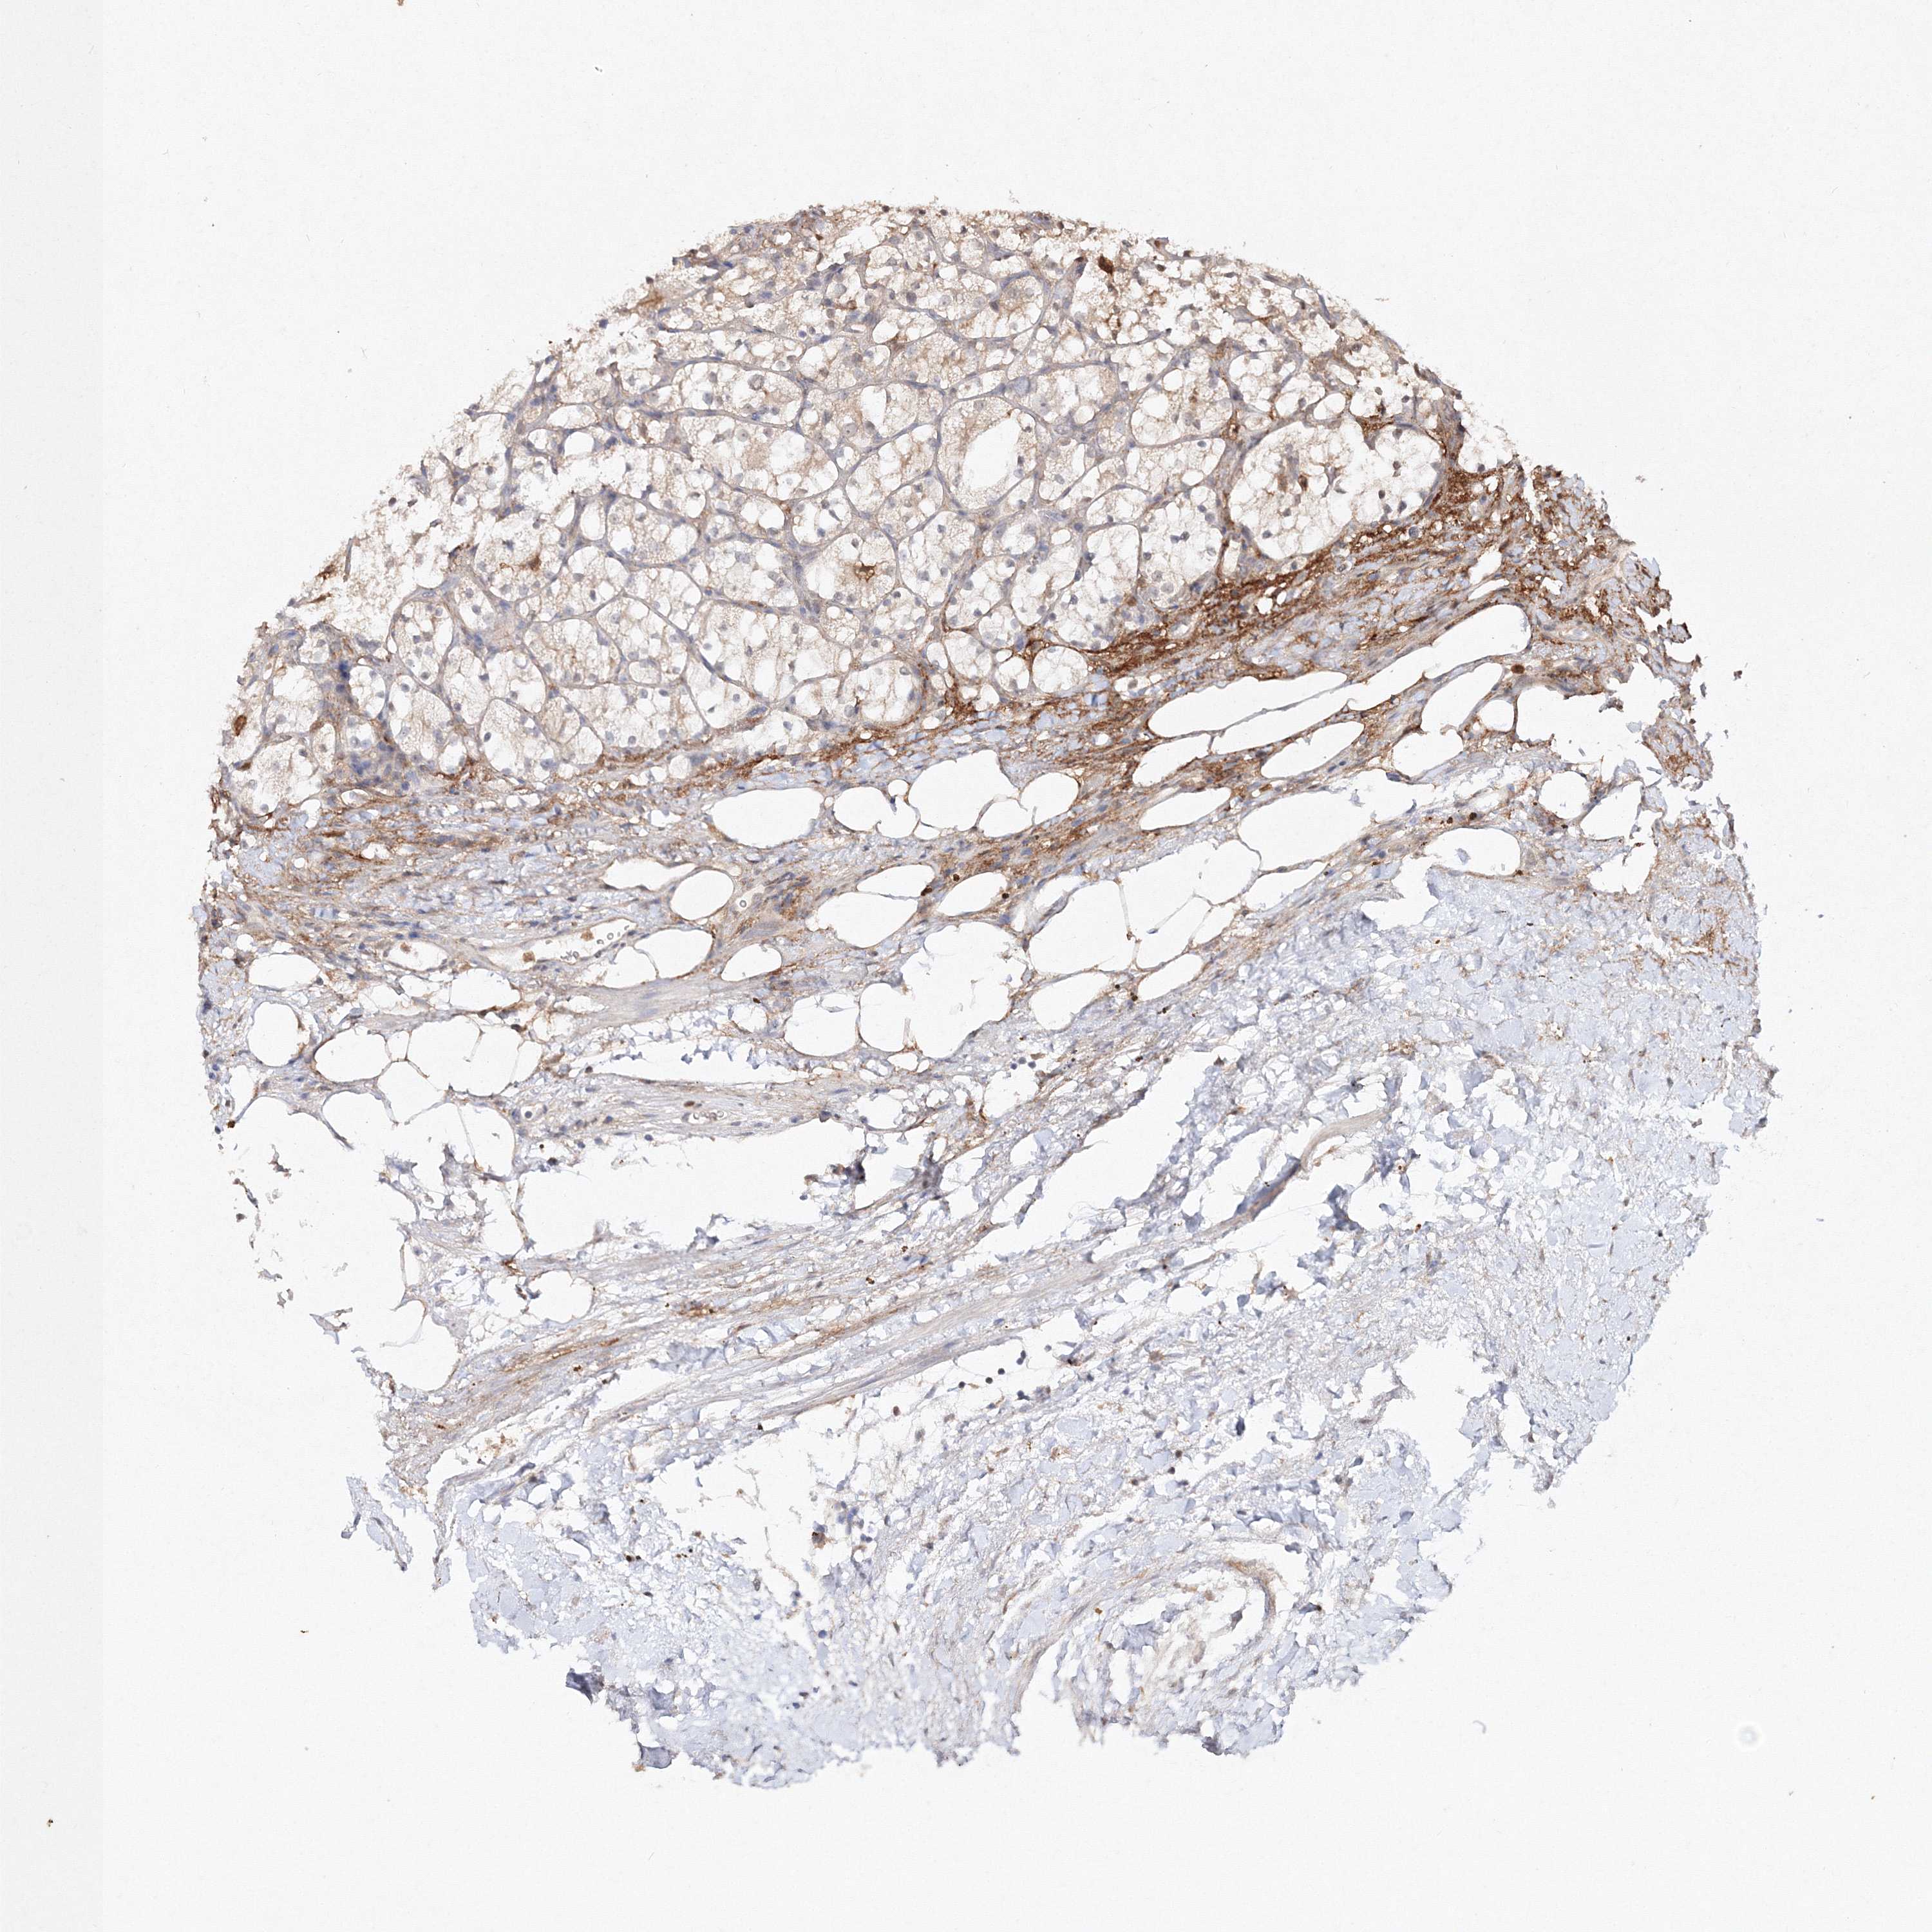

KIDNEY RENAL PAPILLARY CELL CARCINOMA (TCGA) - Interactive survival scatter ploti

The Survival Scatter plot shows the clinical status (i.e. dead or alive) for all individuals in the patient cohort, based on the same data that underlies the corresponding Kaplan-Meier plots. Patients that are alive at last time for follow-up are shown in blue and patients who have died during the study are shown in red.

The x-axis shows the expression levels (FPKM) of the investigated gene in the tumor tissue at the time of diagnosis. The y-axis shows the follow-up time after diagnosis (years). Both axes are complimented with kernel density curves demonstrating the data density over the axes. The top density plot shows the expression levels (FPKM) distribution among dead (red) and alive patients (blue). The right density plot shows the data density of the survived years of dead patients with high and low expression levels respectively, stratified using the cutoff indicated by the vertical dashed line through the Survival Scatter plot. This cutoff is automatically defined based on the FPKM cutoff that minimizes the p-score. The cutoff can be changed by dragging the vertical line or by entering a cutoff value in the square labeled "Current cut-off".

Under the Survival Scatter plot the p-score landscape (black curve; left axis) is shown together with dead median separation (red curve; right axis). Dead median separation is the difference in median mRNA expression between patients who have died with high and low expression, respectively. It is calculated as follows: median FPKM expression of dead patients with high expression - median FPKM expression of dead patients with low expression. This is intended to aid the user in visually exploring custom cutoffs and the associated p-scores and dead median separation.